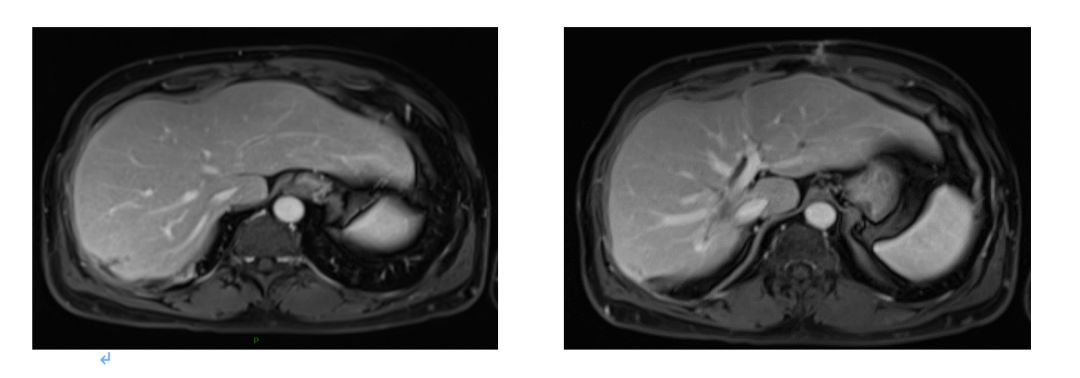

2015.9 肝S8段病灶区域DT45Gy/15F放疗。

2016.4.28肝脏MRI:治疗后改变。

2017.6复查肝脏再次出现新病灶,右后叶包膜下边缘见2.2cm*1.4cm强化结节。

2017.6.6行腹腔粘连松解术+肝转移瘤切除术;

术后病理(肝右叶)绒毛管状腺癌,结合临床病史,符合结肠癌肝转移。

2017.7行肝转移灶术后瘤床放疗DT36Gy/6F;

2019.7.18复查MRI无异常。